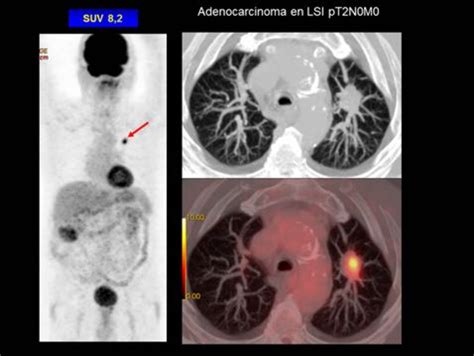

Imagen Metabólica en Neumología: PET-TC

La tomografía por emisión de positrones (PET), especialmente combinada con la tomografía computarizada (TC) en equipos PET-TC, ha revolucionado el diagnóstico por imagen en neumología, particularmente en el manejo de enfermedades neoplásicas.

La PET-TC fusiona la información anatómica de la TC con la información metabólica de la PET (utilizando trazadores como la 2-[18F]fluoro-2-desoxi-D-glucosa (18F-FDG)), lo que mejora significativamente la precisión diagnóstica al reducir falsos negativos y positivos.

Aplicaciones en Neumología

- Carcinoma Pulmonar No Microcítico (CPNM): La PET-TC es fundamental para la estadificación del CPNM, determinando la extensión del tumor primario (T), la afectación de ganglios linfáticos (N) y la presencia de metástasis (M).

- Nódulo Pulmonar Solitario (NPS): La PET-TC ayuda a caracterizar nódulos pulmonares, diferenciando entre benignos y malignos. La captación de 18F-FDG por el nódulo se relaciona con su tamaño y actividad metabólica.

La PET-TC mejora la eficacia diagnóstica al combinar datos anatómicos y metabólicos, siendo una herramienta valiosa en el arsenal diagnóstico actual para el paciente oncológico.